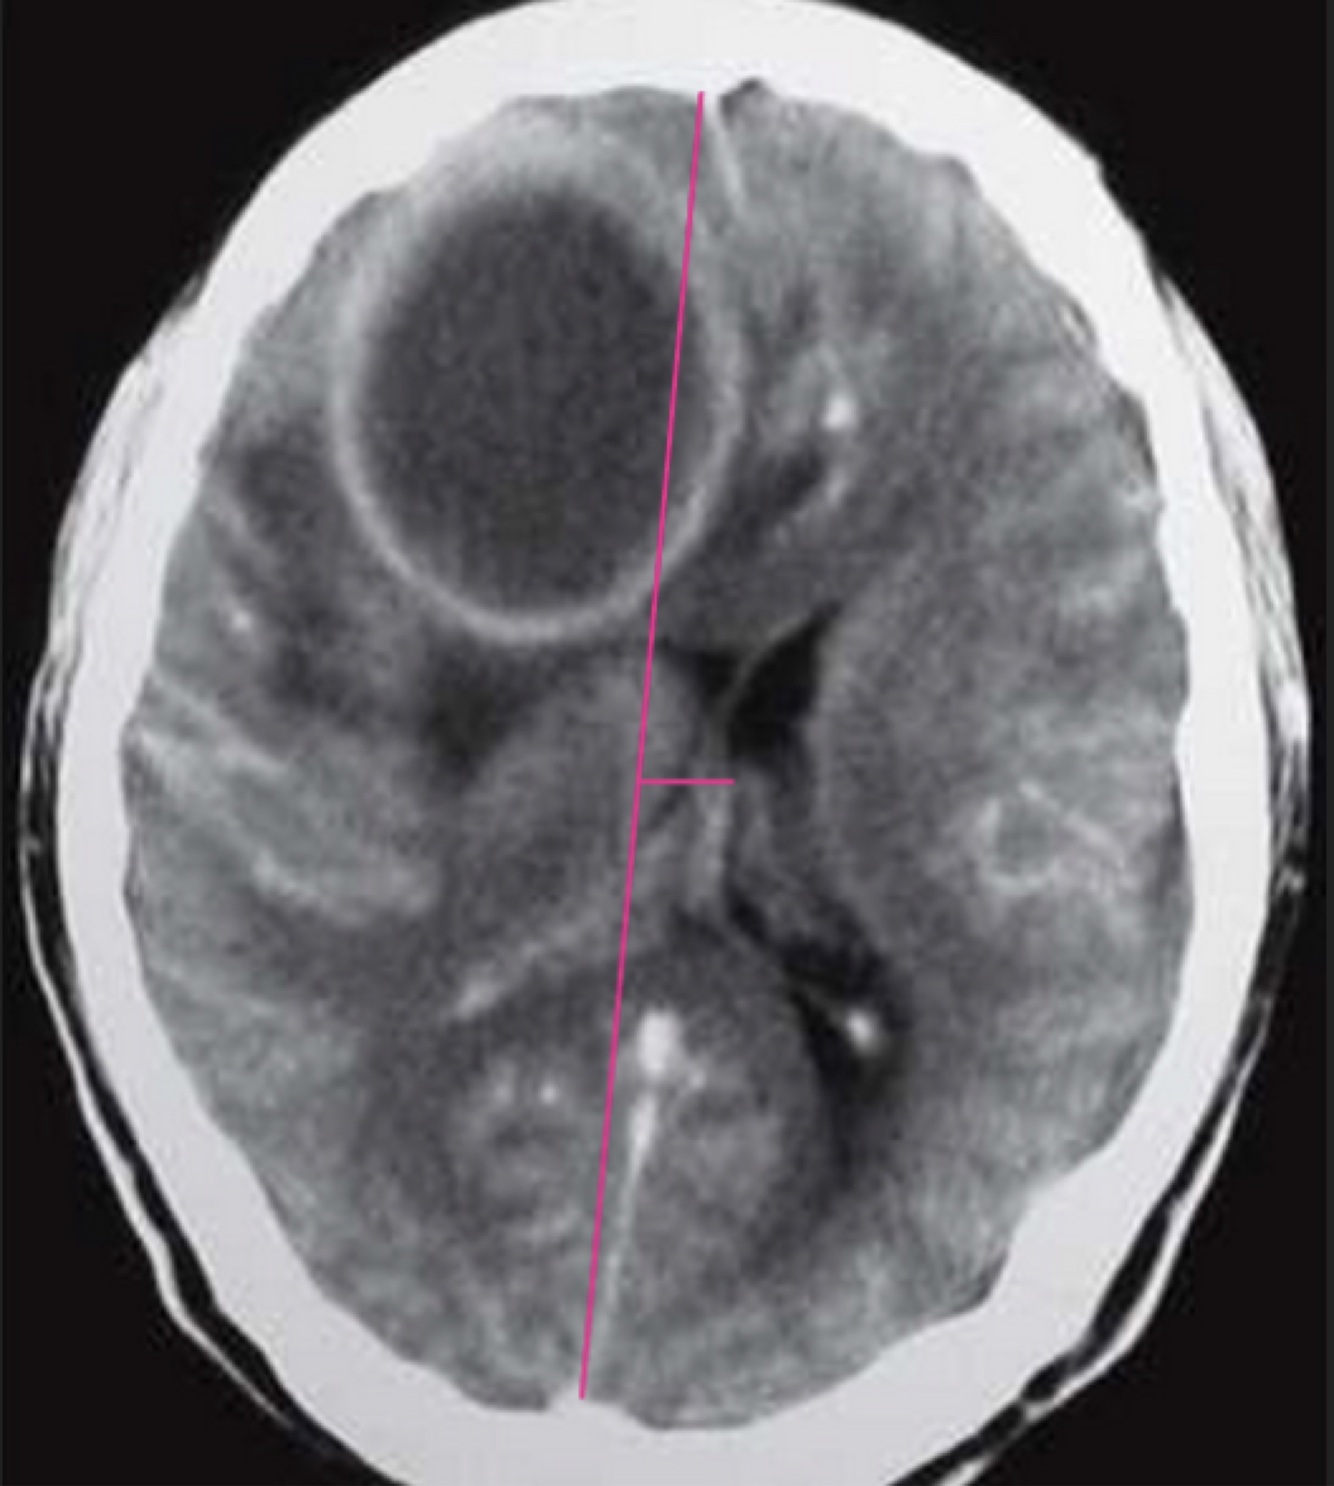

Q

Hay desviación de la línea media en SNC?

A

VERDADERO